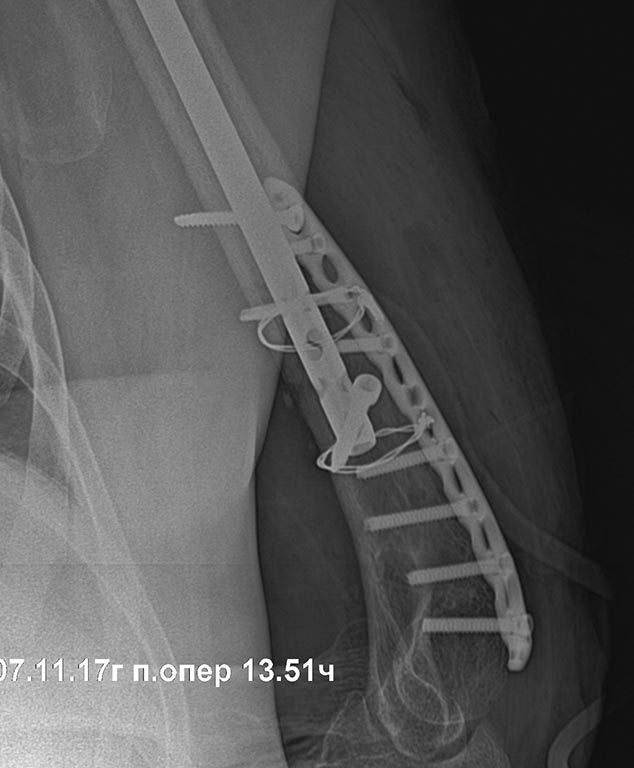

Отправитель: Стас 07 Ноябрь 2017, 16:58

контроль

Отправитель: Стас 07 Ноябрь 2017, 17:01

боковая